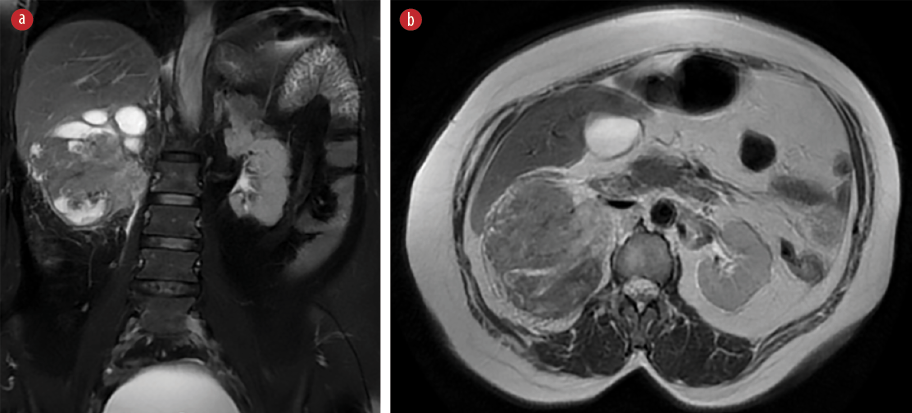

A CT scan showed a large tumor occupying the whole right kidney [Figure 5]. Magnetic resonance imaging of the abdomen revealed a large heterogeneous lesion occupying the right kidney, highly suggestive of a neoplastic etiology. Multiple enlarged retroperitoneal lymph nodes were also visualized. There was a loss of fat plane between the right colon and the mass [Figures 6 and 7]. The patient underwent open right radical nephrectomy, along with an excision of the nephrocutaneous fistula tract. Due to adhesions with the right colon and suspected local invasion, enbloc resection with right hemicolectomy was also performed.

Figure 6: (Case 2) Magnetic resonance imaging of abdomen showing a large heterogeneous lesion occupying the right kidney, highly suggestive of a neoplastic etiology. (a) Coronal view (b) Axial cut section